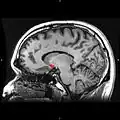

Nucleus accumbens of the mouse brain